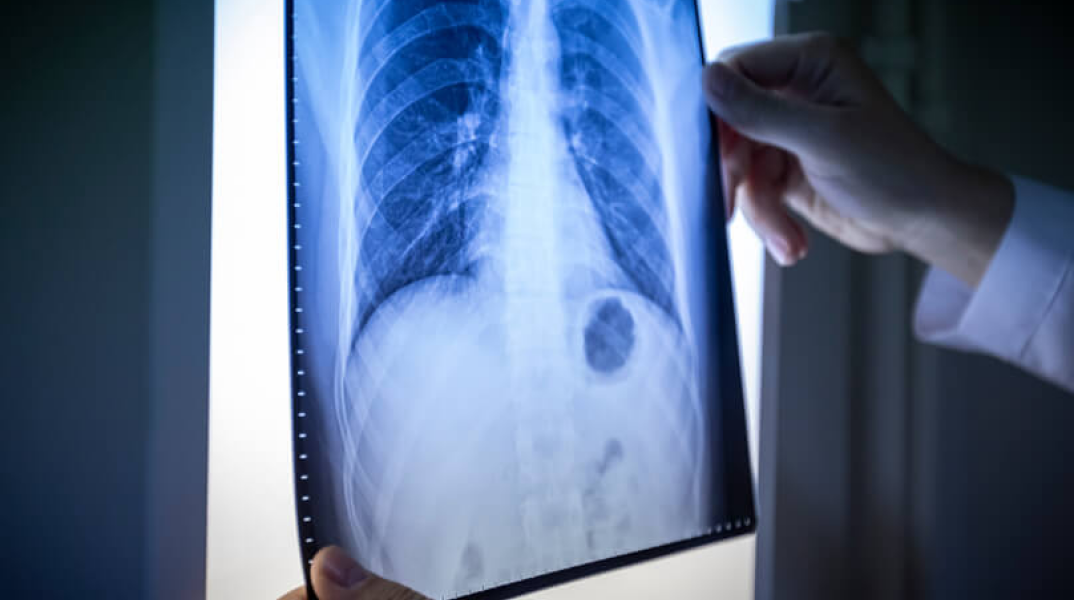

Η διάγνωση επιβεβαιώνεται μέσω της κλινικής εξέτασης, κατά την οποία χαρακτηριστικά ευρήματα, όπως οι τρίζοντες, μπορεί να προηγούνται των ακτινολογικών αλλοιώσεων. Τα ευρήματα αυτά απουσιάζουν συνήθως στις ιογενείς ή άτυπες πνευμονίες. Επιπλέον, η διάγνωση επιβεβαιώνεται από τον ακτινολογικό έλεγχο με ακτινογραφία θώρακος, καθώς είναι εξαιρετικά σπάνιο να παρουσιαστεί πνευμονία με φυσιολογική ακτινογραφία.